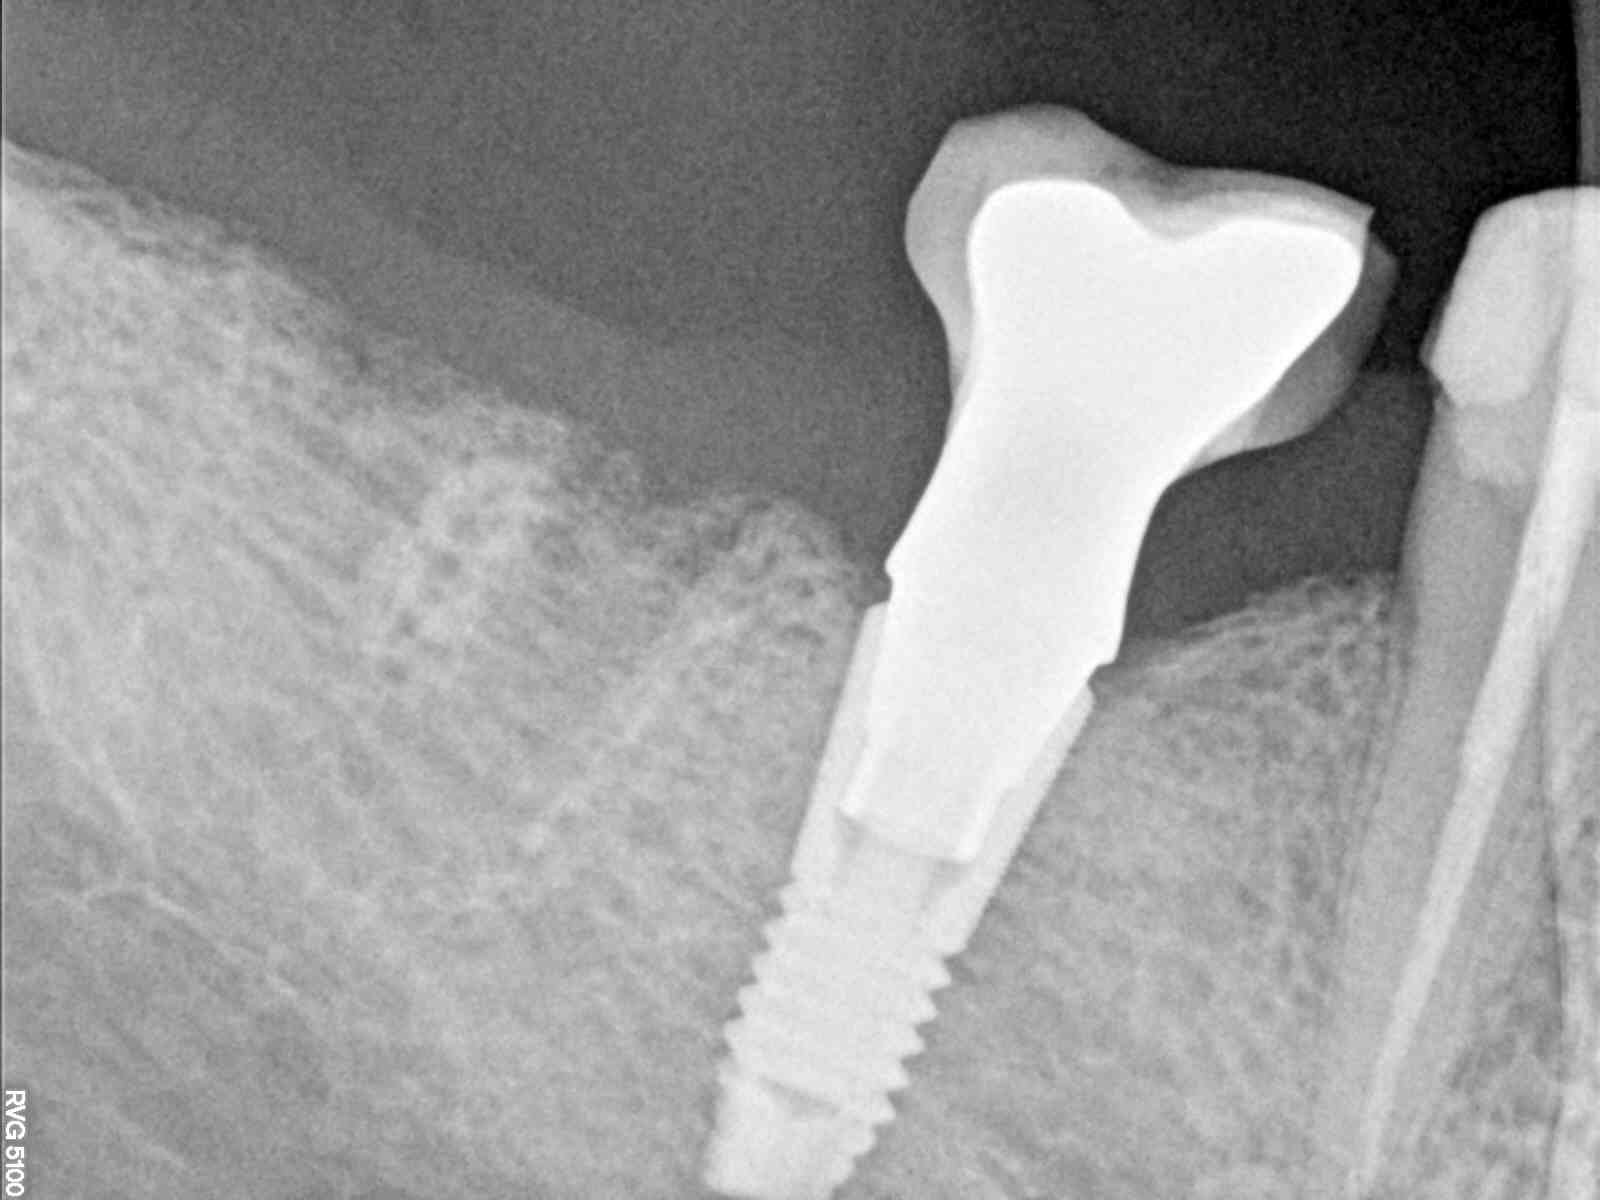

Buenas tardes compañeros, me podeis ayudar con la marca y compatibilidades de este implante? ha fracturado la corona. Creo que es un astra pero no se la métrica, muchas gracias